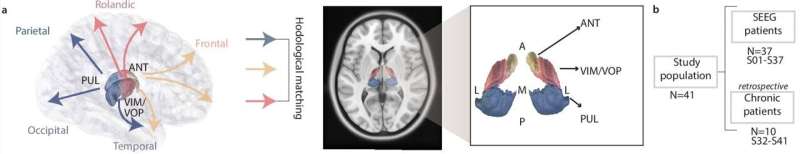

“The existing FDA-cleared therapy targets only one portion of the thalamus, the anterior nucleus,” said lead author Arianna Damiani, M.Sc., a graduate student researcher at Pitt’s Rehab Neural Engineering Laboratories (RNEL).